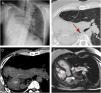

We report the case of a 37-year-old man diagnosed at birth with right pulmonary agenesis with dextrocardia, operated at the age of 8 years for persistent arteriovenous fistula, and a history of recurrent respiratory infections with bronchial hyperreactivity. Imaging tests (Fig. 1) revealed right pulmonary agenesis with left pulmonary compensatory hyperinflation, anterior transmediastinal herniation, and dextrocardia.

(A) Chest X-ray, posteroanterior projection, showing mediastinal and left lung shift toward the right hemithorax caused by absence of the right lung (pulmonary agenesis). (B) Tomographic axial slice showing lung parenchyma view. The arrow indicates the rudimentary right main bronchus terminating in the pleural sac. (C) Tomographic axial slice without intravenous contrast showing the shift of vascular structures toward the right hemithorax, and absence of right pulmonary artery. API: Left pulmonary artery. (D) Cine-MR b-FFE oblique axial slice. Dextrocardia, dextro-apex and complete absence of right lung parenchyma are observed. VD: right ventricle; VI: left ventricle.